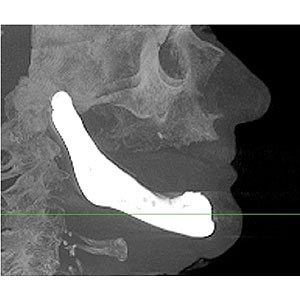

LayerWise applied Additive Manufacturing (AM) to produce an award-winning Titanium total lower jaw implant reconstruction, developed in collaboration with project partners from medical industries and academia. To treat a senior patient's progressive osteomyelitis of almost the entire lower jawbone, medical specialists and surgeons opted for such a complete patient-specific implant the first time ever. AM technology specialists at LayerWise printed the complex implant design incorporating articulated joints and dedicated features. The reconstruction - post-processed with dental suprastructure provisions, polished joint surfaces and a bioceramic coating â?? has been implanted successfully. It restored the patientâ??s facial esthetics and allowed her to regain her speech within hours.

LayerWise in Leuven, Belgium, produced the metal implant structure layer by layer using its dedicated metal AM technology. A high-precision laser selectively heats metal powder particles, in order to quickly and fully melt to properly attach to the previous layer without glue or binder liquid. As layers are built successively, AM hardly faces any restrictions to produce the complex lower jaw implant structure. AM is used to print functional implant shapes that otherwise require multiple metalworking steps or even cannot be produced any other way.

Prof. Dr. Jules Poukens of the University Hasselt: 'The new treatment method is a world premiere because it concerns the first patient-specific implant in replacement of the entire lower jaw. The implant integrates multiple functions, including dimples increasing the surface area, cavities promoting muscle attachment, and sleeves to lead mandible nerves. Furthermore, the mandible implant is equipped to directly insert dental bar and/or bridge implant suprastructures at a later stage. I led the team of surgeons who implanted the AM-produced structure during a surgery of less than four hours at the Orbis Medisch Centrum in Sittard-Geleen. Shortly after waking up from the anesthetics the patient spoke a few words, and the day after the patient was able to speak and swallow normally again.'